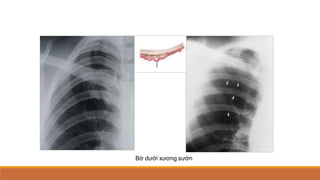

Khung xương

Bờ dưới xương sườn

Bờ dưới xương sườn vùng giữa và thấp dạng dải mờ (tránh lầm phản ứng màng xương)

Đầu xương sườn phía sau khớp vào thân

sống và mỏm ngang 

tránh lầm gãy

xương sườn